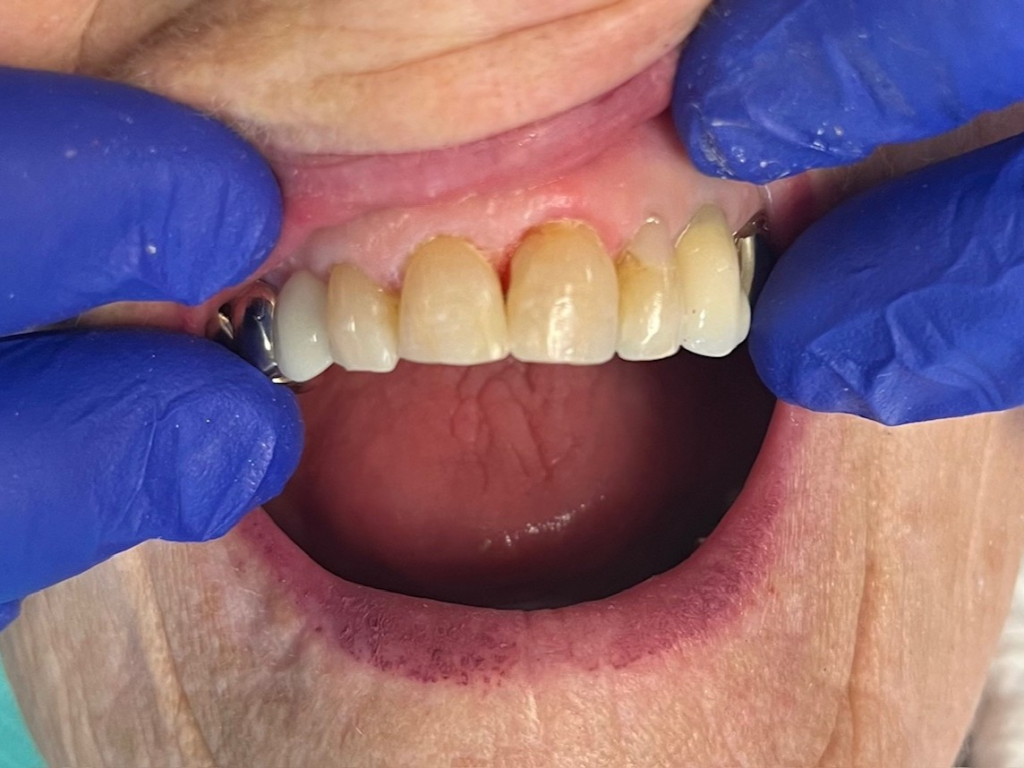

Anterior broken tooth. Double DentXpinTM repair.